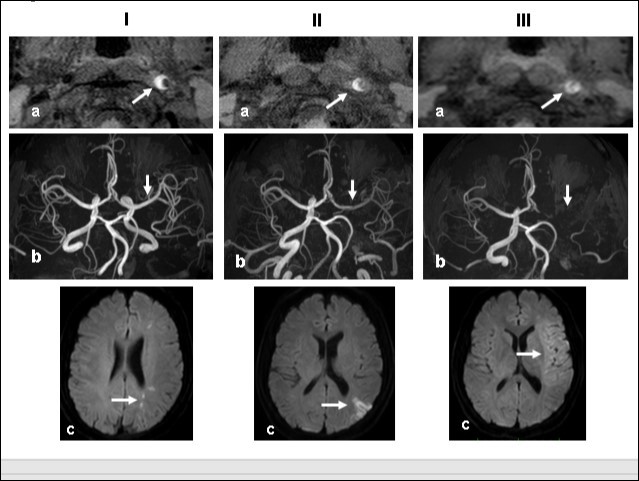

This 43-year-old Japanese male presented with right hand dysesthesia. He has not recognized his neck pain and Horner’s syndrome( oculosympathetic palsy). Magnetic resonance imaging(MRI) performed on a 3T TX scanner (Philips Achieva, The Netherlands) demonstrated dissection of the left cervical carotid artery (CCA; Figure 1A,1B ); no ischemic area was detected in the left cerebral brain. Axial section views of the CCA segment revealed a typical crescent hematoma; a bright, hyper-intense circle representing the narrowed arterial lumen was visualized. A T1-volumetric isotropic turbo spin echo acquisition (VISTA) sequence resulted in the diagnosis of dissection of the CS-ICA (Figure 1C). He had no conventional stroke risk factors such as hypertension, diabetes, hyperlipidemia, a history of cardiac valvular disease, arterial fibrillation, or features of inherited connective tissue disorder. Also absent was a history of arterial trauma and we were unable to identify any etiological factor(s). One week later he developed Gerstman symptoms; border zone ischemia was observed in the left cerebrum (Figure 2-Ic). He was admitted and the administration of antiplatelet agents was started. The left middle cerebral artery (MCA) was supplied via antegrade circulation (Figure 2-Ib) and an increase in the flow-void intensity was noted (compare Figure 1C with Figure 2-Ia). MRI studies acquired one week later revealed spreading of the ischemic area to beyond the watershed zone between the left anterior cerebral artery (ACA) and the MCA, and the MCA and the posterior cerebral artery (PCA) (Figure 2-IIc). The area of dissection had spread from the ICA bifurcation to the top of the ICA. The blood supply to the left MCA territory derived from the circle of Willis (Figure 2-IIb). The flow-void intensity had increased further (compare Figure 2-Ia with Figure 2-IIa). Two weeks after his admission he suddenly experienced complete right-sided hemiparesis with motor aphasia. MRI performed within 45 min demonstrated diffuse ischemia in the left MCA territory (Figure 2-IIIc), the left A1 segment could not be visualized. The left MCA and its A1 segment were completely occluded (Figure 2- IIIb). The flow-void intensity indicated complete occlusion of the true lumen (Figure 2-IIIa). He underwent emergency left superficial temporal artery (STA)-MCA bypass surgery within 6 hours; double anastomosis was successful. External decompression was performed to prevent neurological deterioration due to severe brain swelling. An intensive rehabilitation has been continued for him after operation. His functional independence measure (FIM) score recorded over the course of 4 months showed remarkable improvement ( Figure 3) as did the standard language test for aphasia.

Figure 2.Time course Columns I, II, and III are images obtained 1, 2, and 3 weeks, respectively, after the start of dissection of the cervical segment of the internal carotid artery. Ia, IIa, IIIa.T1 VISTA images of the same segment shown in Fig. 1C. The dark area reflective of the low void progresses to hyperintensity by week 3. IIIa shows complete occlusion of the true lumen by the intramural hematoma (arrow ). Ib, IIb, IIIb. TOF-MRA images of the intracranial arteries. (a) The left MCA is supplied via antegrade flow from the left carotid artery (arrow). (b) Flow from the left carotid artery disappeared from the ICA bifurcation to the top of the ICA. Blood supply to the left MCA derives from the circle of Willis via the anterior- or the posterior communicating artery (arrows). By week 3, flow to the left MCA, even via the left A1 segment of the anterior cerebral artery had disappeared completely. Ic, IIc, IIIc. Diffusion-weighted images at the basal ganglia level. Week 1: a few hyperintense areas are visualized in the border zone of the left cerebrum (arrow). Week 2: Note the hyperintensity area in the watershed zone between the left ACA and the MCA, and between he MCA and the PCA (arrow). The image acquired on week 3 shows a diffuse hyperintensity area in the left MCA territory (arrow).